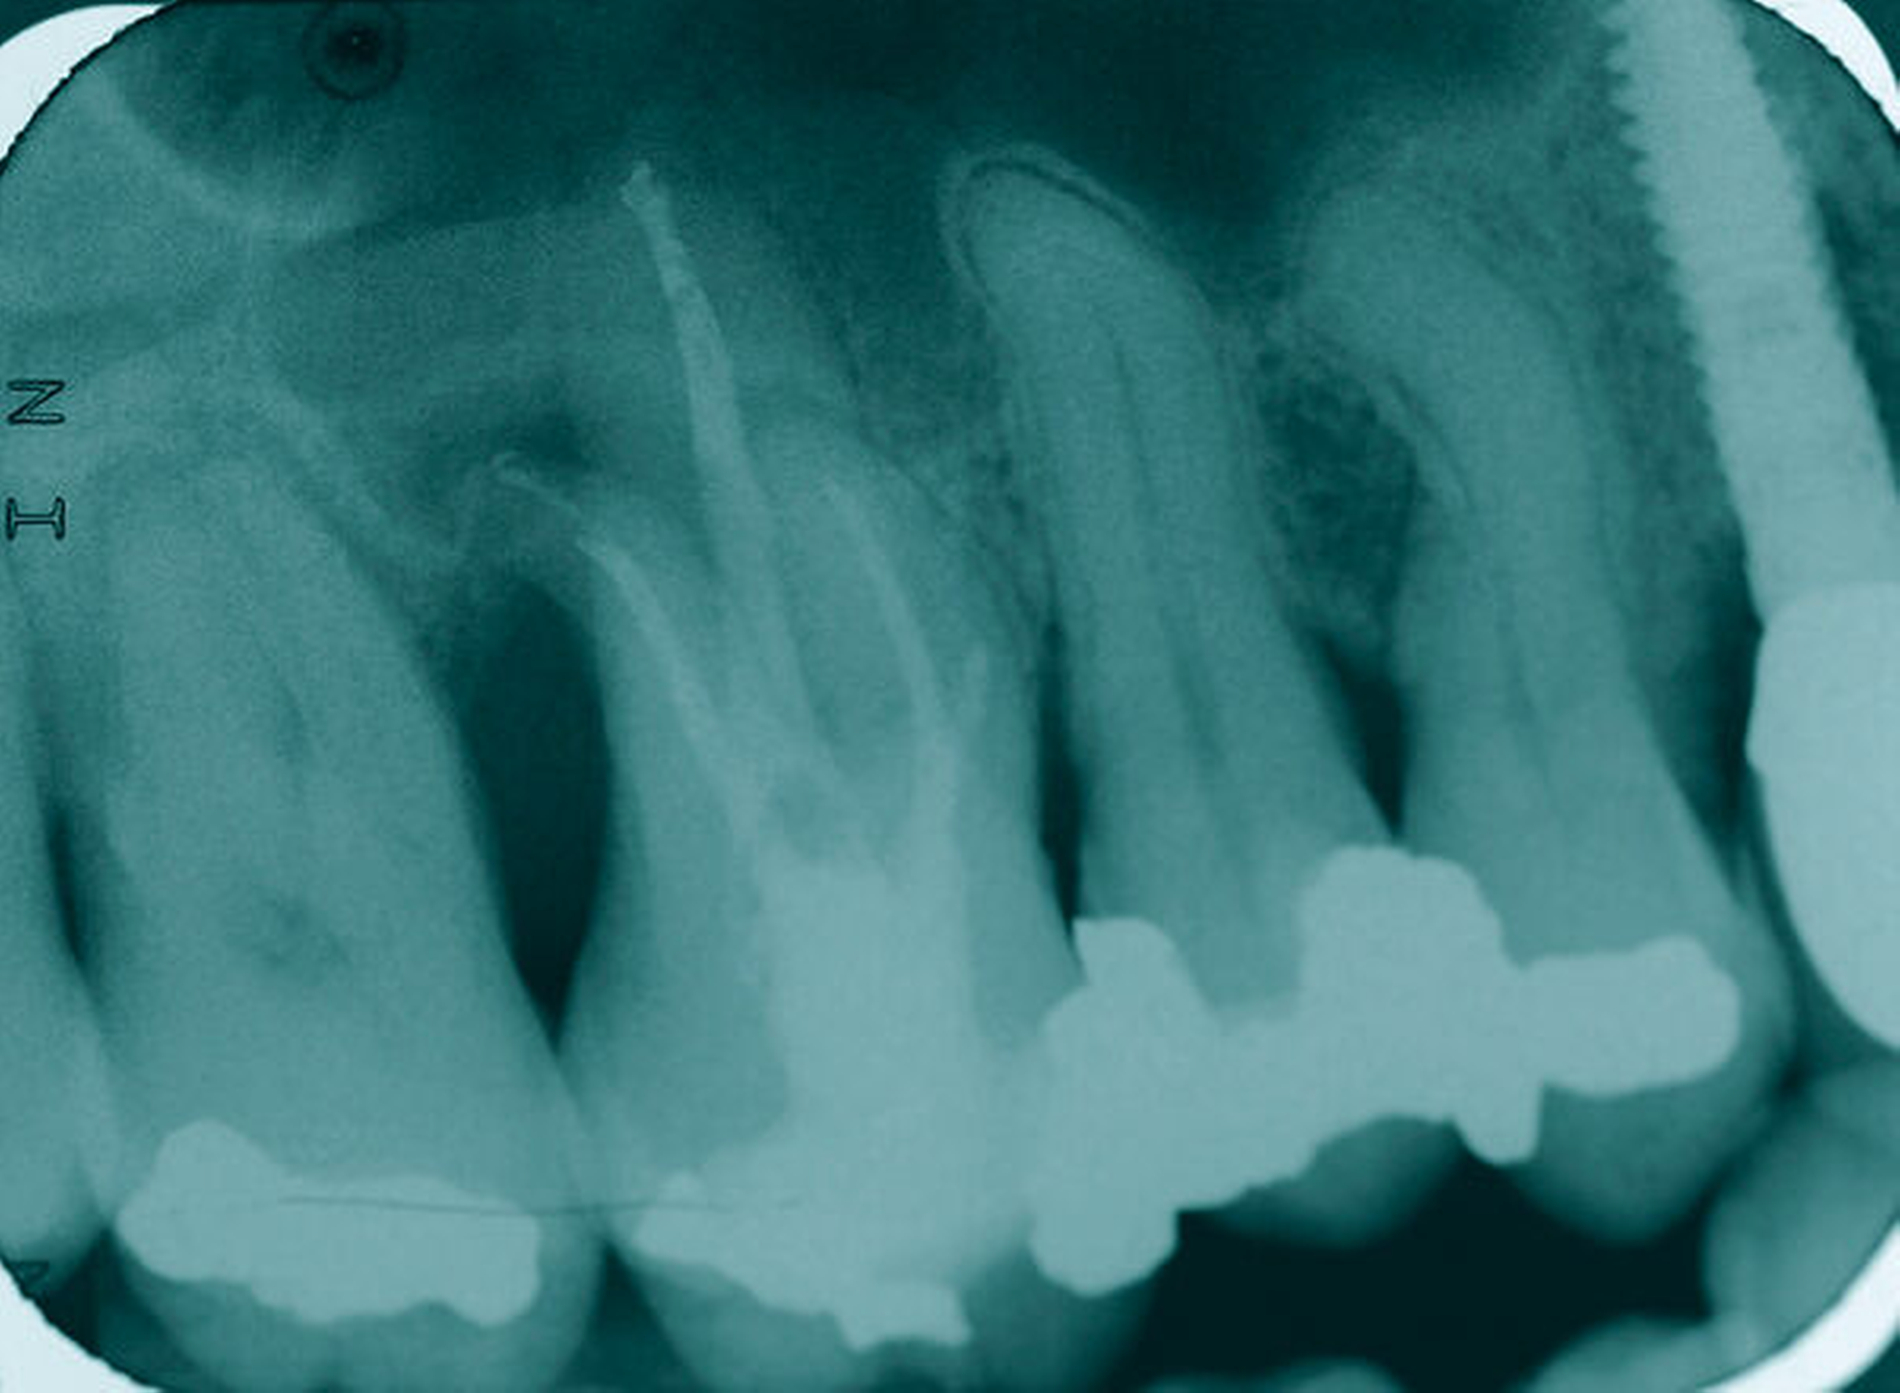

Ein 59-jähriger Patient stellte sich erstmals 2015 mit rezidivierenden pochenden Beschwerden und zeitweise zusätzlich auftretendem Pusaustritt an Zahn 16 vor. Klinisch zeigte sich ein ausgeprägter Attachmentverlust distal mit bis apikal sondierbarer distobukkaler Wurzel, Furkationsbeteiligung und Pusaustritt sowohl über den Parodontalspalt als auch durch einen distobukkal gelegenen Fistelausgang. Zunächst erfolgte die endodontische Behandlung des Zahnes 16 mit anschließender systematischer PA-Therapie. Bei persistierender parodontaler Problematik an 16 wurde die Möglichkeit der Teilamputation der distobukkalen Wurzel mit dem Patienten diskutiert, um die Hygienefähigkeit und damit die Prognose des Zahnes zu verbessern. Auch über die Extraktion als Alternative wurde der Patient aufgeklärt. Er war allerdings motiviert, seinen Zahn so lange wie möglich zu erhalten.

So erfolgte die Amputation der distobukkalen Wurzel mit anschließender Versorgung des Zahnes mittels Vollkrone. Die Situation an 16 ist seitdem für den Patienten subjektiv stabil, die aktuelle Röntgenkontrolle zeigt jedoch eine Progredienz der parodontalen Defekte trotz regelmäßiger UPT und subjektiv guter Mitarbeit des Patienten, was die Prognose des Zahnes negativ beeinflusst. Ursächlich hierfür kann eine persistierende parodontale Infektion durch den trotz Wurzelamputation immer noch schwer für die häusliche Mundhygiene zugänglichen Furkationsbereich mit enger Lagebeziehung der mesiobukkalen und der palatinalen Wurzel sein. Der Patient ist allerdings aktuell mit der Situation zufrieden und beschwerdefrei und wünscht daher noch keine Extraktion des Zahnes, auch wenn diese sich nun fünf Jahre nach dem initialen Befund nicht mehr sehr lange vermeiden lassen wird.